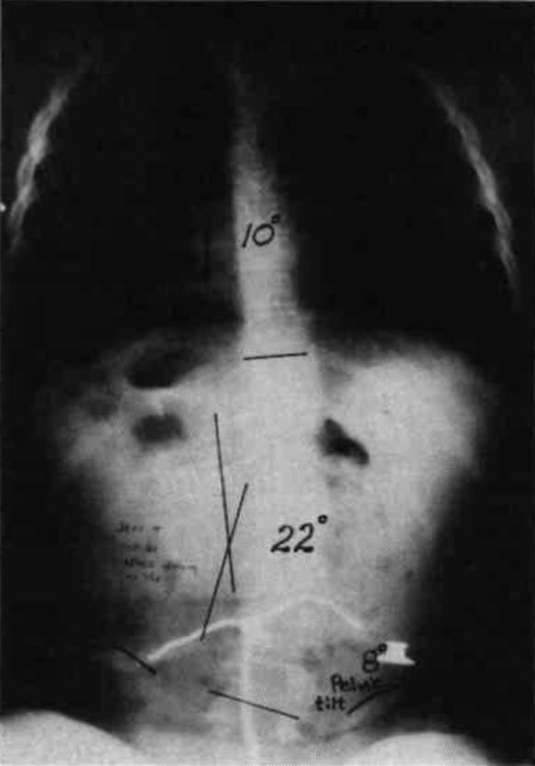

Figure 7. The diagrams on the left illustrate the similarity between the spinal column in the case of an uncontrolled pelvis and the slender column pin-jointed (free to tilt) at its lower end. The two diagrams on the right illustrate the similarity between the controlled pelvic case and the built-in base end condition.To fully appreciate the strength of this scheme in practice, compare the two x-rays in Fig. 8a and Fig. 8b. Fig. 8a is the x-ray taken just before the pelvic leveling procedure was performed and Fig. 8b is the x-ray taken a few minutes later, after the pelvic leveling procedure was performed. The Cobb angle is reduced from 36 degrees to 20 degrees by this quick procedure, which is normally performed as a routine part of positioning the child in the sitting support orthosis. These x-rays are of a boy with Duchenne Muscular Dystrophy; he was not wearing a corset.

Figure 8a. An x-ray taken just before the pelvic leveling procedure was performed.Figure 8b. The x-ray taken a few minutes later after the procedure.

A second example is given in Fig. 9. The left and center x-rays show the progression which occurred in the eight months following fitting. During this period, the parents did not use the pelvic leveling procedure. The x-ray on the right was taken a short time after the center x-ray, with the only difference being the pelvic leveling procedure was performed before the last film. Note: once a spine deformity has become partially structural, the pelvis can be leveled only to the degree that the deformity is still flexible.

Figure 9. The left and center x-rays show the progression which occured in eight months following a fitting. During this period, the parents did not use the pelvic leveling procedure. The x-ray on the right was taken a short time after the center x-ray, and after the pelvic leveling procedure was performed.In summary, maintaining a level pelvis makes it easier to control the spine. Pelvic control and orientation in the frontal plane also relates strongly to the uniformity of pressures in weight bearing areas and minimizing the progressive deterioration of sitting comfort.